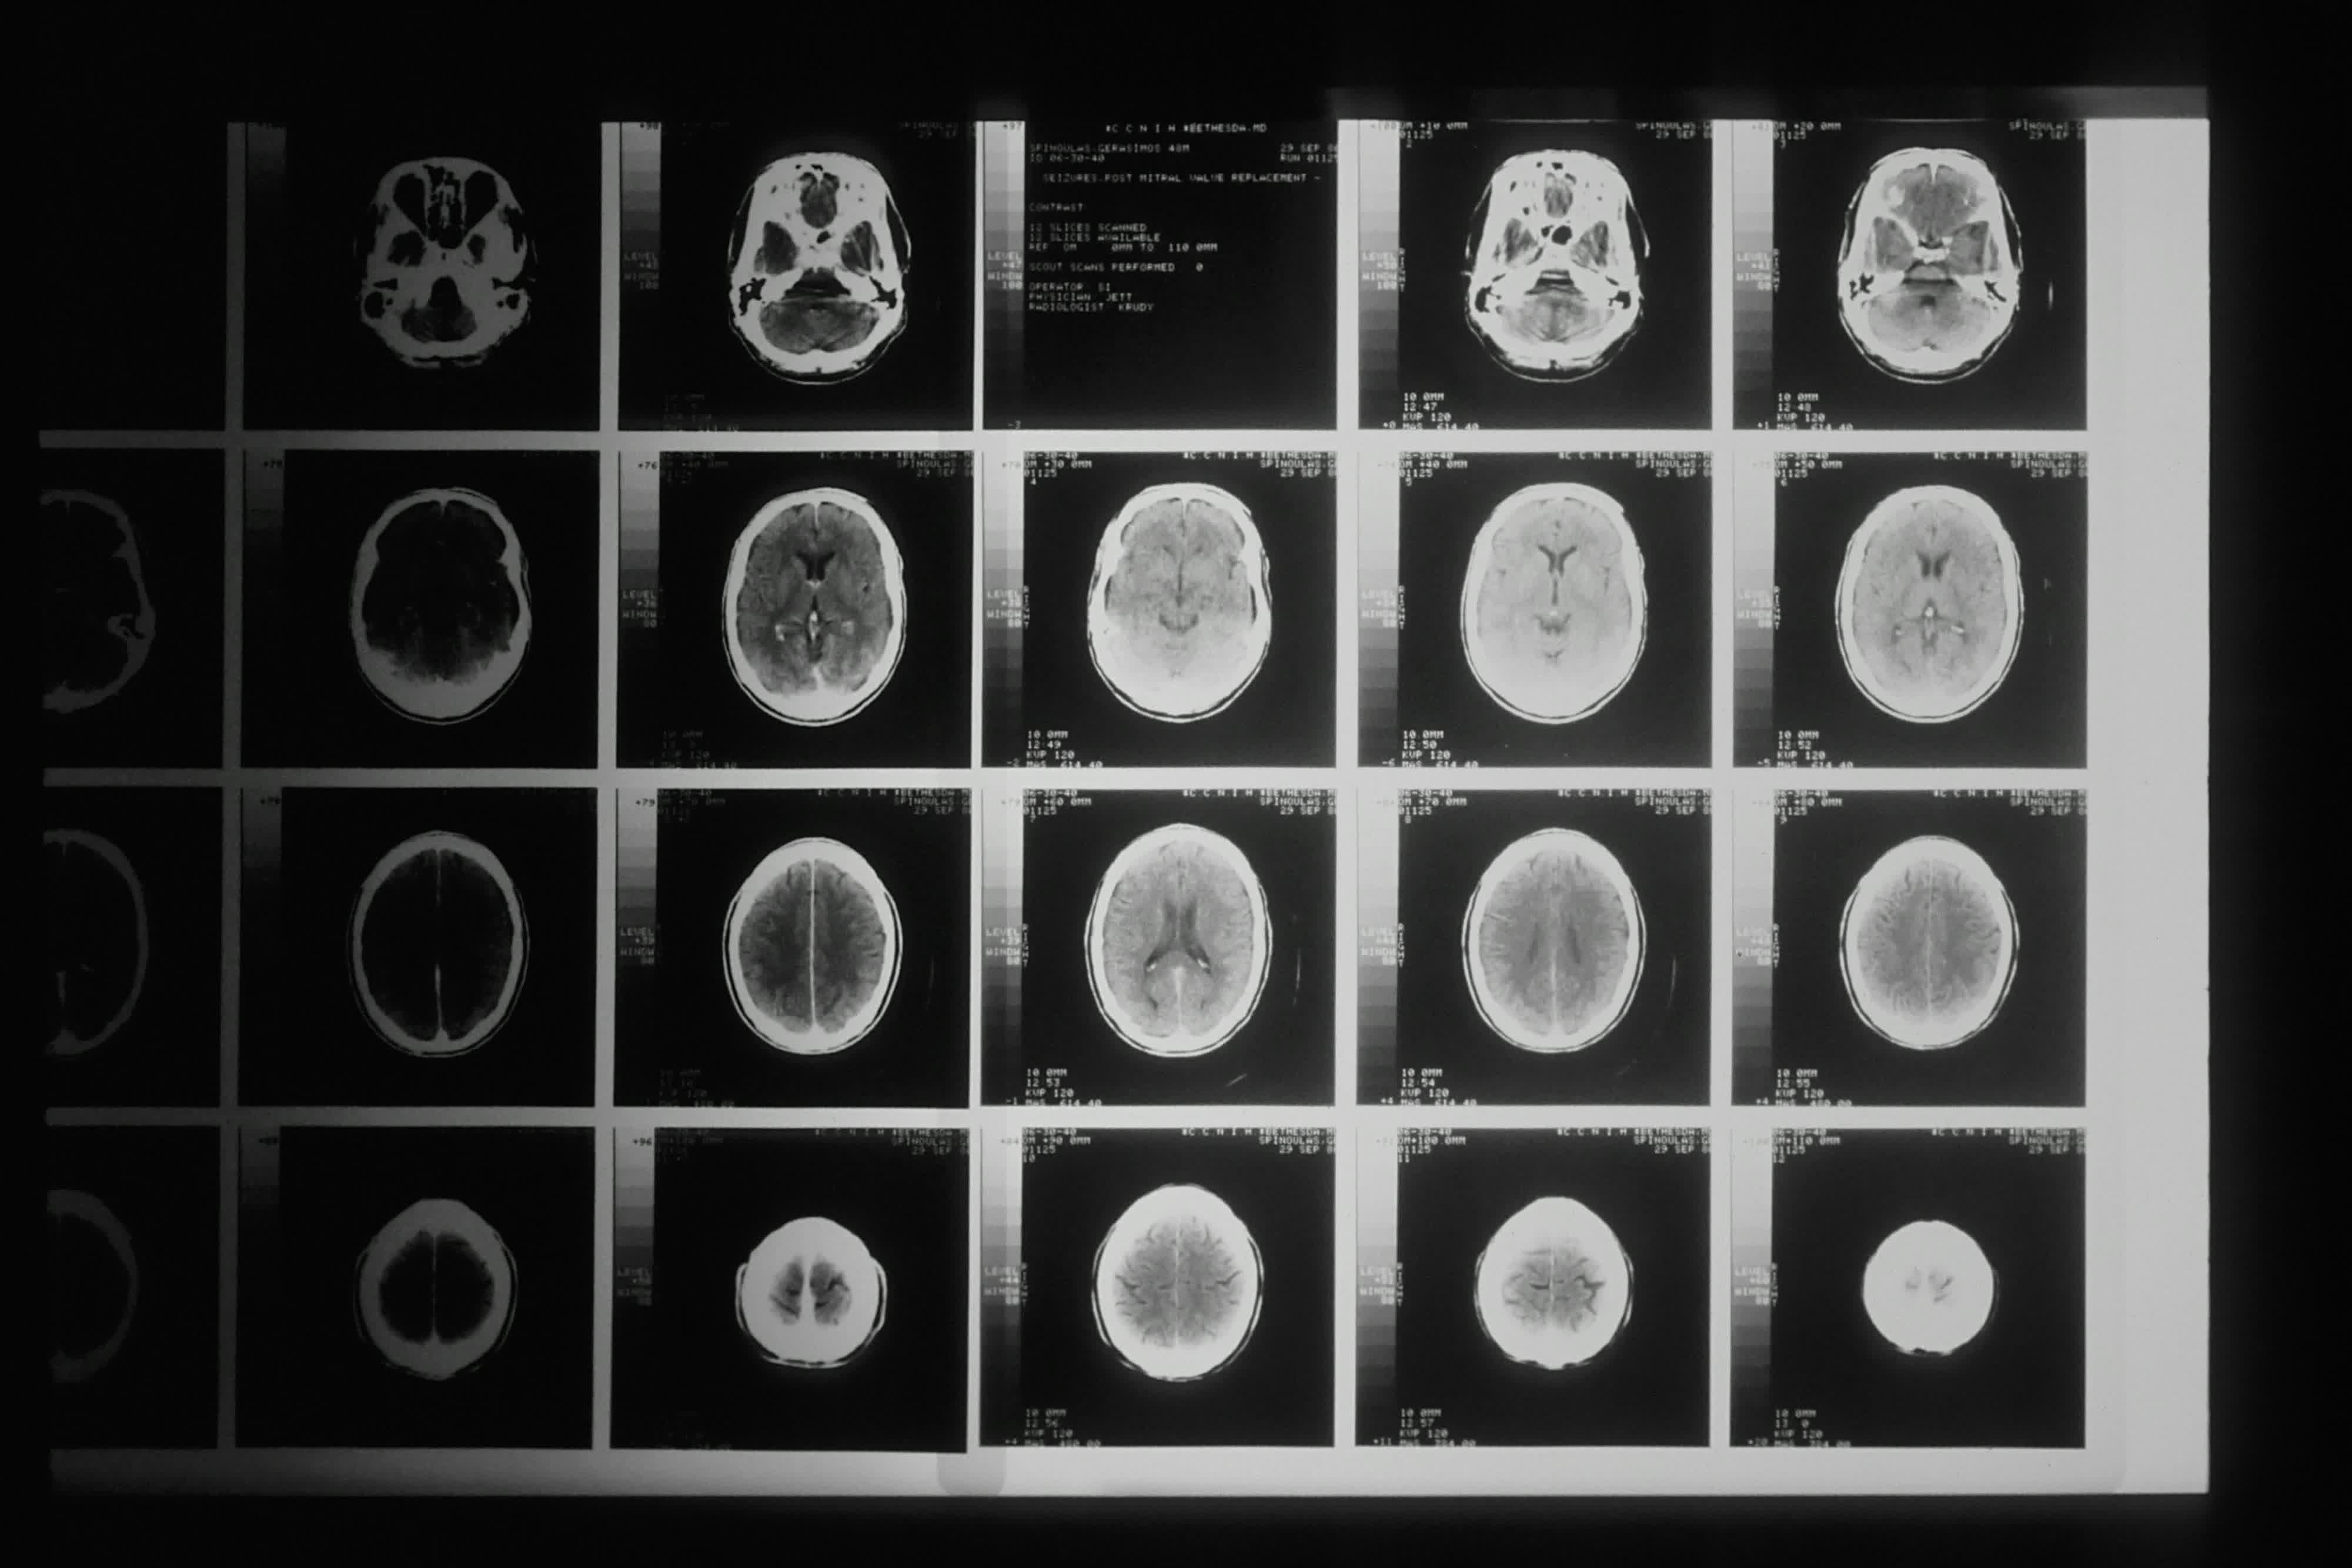

A hot potato: A new study from UC San Francisco is raising alarms about the widespread use of computed tomography (CT) scans in the United States, warning that the technology may be responsible for as much as 5 percent of all cancers diagnosed each year. The research, published in JAMA Internal Medicine and funded by the National Institutes of Health, suggests that the risks associated with CT scans – particularly the exposure to ionizing radiation – are far greater than previously believed.

CT scans, also known as CAT scans, have become a mainstay in modern medicine, used to detect tumors and diagnose a wide range of illnesses. Since 2007, the number of annual CT exams in the US has jumped by 30 percent. In 2023 alone, Americans underwent 93 million CT scans, a figure that researchers say could result in nearly 103,000 new cancer cases – three to four times higher than previous estimates.

The findings indicated that the excess cancer risks associated with CT scans also apply to the youngest patients and, again, are higher than previously recognized. Researchers analyzed data from 93 million CT exams performed on 61.5 million patients across the country. The likelihood of receiving a scan increased with age, peaking among adults aged 60 to 69. Children made up just over 4 percent of the scans, but the risks for this group were particularly acute. The study excluded scans performed in the last year of a patient's life, as these were unlikely to contribute to future cancer cases.

For children, the most frequently projected cancers were thyroid, lung, and breast. The data showed that CT scans of the abdomen and pelvis were the largest contributors to cancer risk in adults, while head scans posed the greatest risk for children. Notably, infants who underwent CT scans were found to be ten times more likely to develop cancer compared to other age groups.